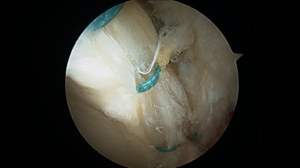

Hip Impingement Arlington VATo relieve severe hip pain and prevent joint degeneration, a physician may suggest a surgical procedure to remove excess bone and provide clearance for the labrum. Once the excess bone has been removed, the labrum is reattached with anchors and surgical string to the rim of the socket to re-establish the joint seal. More importantly, at the same time, any FAI is addressed by reshaping the bone to eliminate the impingement. Following surgery, patients are typically weight bearing as tolerated (meaning they can put as much weight on their leg as feels comfortable), and they are in a hip brace for usually 4-6 weeks. Dr. Ochiai’s rehab starts IMMEDIATELY after surgery with passive range of motion exercises, and formal physical therapy is typically started within two weeks.